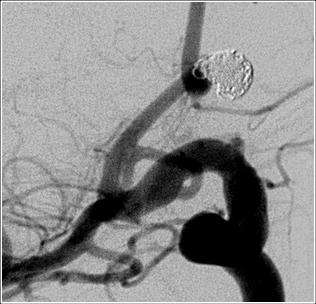

The modern treatment of aneurysms include surgical clipping, endovascular coiling, floater diversion, vessel sacrifice and observation of the aneurysm. (Figures 3, 4, and 5). The selection of therapy depends upon multiple factors including patient's age, disease state, medical conditions, aneurysm size and location.

ruptured before 2a

ruptured after 2a

Figure 3. Before Treatment: Hemorrhagic stroke from ruptured intracranial aneurysm.

Figure 4. After Treatment: Bleeding is arrested using detachable coil.